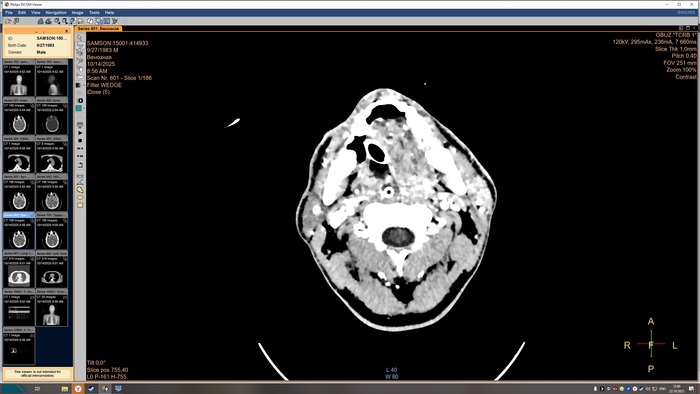

Описание КТ прикрепляю, а снимки будут в конце поста, по-другому у меня не получилось.

На топограмме, серии аксиальных срезов и реконструкций получены изображения суб- и

супратенториальных структур головного мозга от большого затылочного отверстия до крыши

черепа в нативном виде и в/в контрастированием. Определяются: справа четко

идентифицируемые внутричерепные интрапаренхиматозные гиперденсные неоднородные

очаги, копящее контрастное вещество, плотностью до 51-55ед.Х., размером: в проекции

лучистого венца 8х8х9 мм, в проекции продолговатого мозга 21х26х19 мм, Срединные

структуры мозга не смещены. Боковые желудочки: правый до 10,2 мм, левый до 12,9 мм,

третий-2,6 мм, четвёртый-13,8 мм. Селлярная и хиазмальная области без видимых

патологических изменений. Цистерны основания мозга, конвекситальные ликворные

пространства и борозды полушарий большого мозга сужены. Оболочки мозга без

особенностей. Миндалины мозжечка расположены соответственно возрасту. Дополнительных

образований и жидкостных скоплений в воздухоносных полостях височных костей с обеих

сторон, полости носа и его придаточных пазух не выявлено. Содержимое глазниц

визуализируется без особенностей. Признаков остеолитического, -пластического процессов,

аномалий развития и/или травматических повреждений костей черепа исследованного уровня

Заключение

КТ-признаки очаговых образований головного мозга. КТ-признаки правосторонней

верхнедолевой сегментарной б/пневмонии. ДИ ГОП.

Снимки КТ